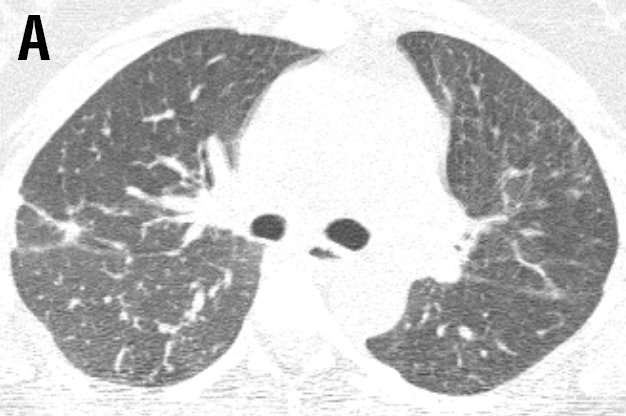

A 40-year-old female was referred to the ild care centre of the MUMC (a tertiary referral centre for sarcoidosis in the Netherlands) with refractory sarcoidosis. She was suffering from severe fatigue, shortness of breath on exertion, coughing, arthralgia and skin lesions, and also described exercise intolerance. She had no other medical history of note. An open lung biopsy showed non-caseating granulomatous inflammation consistent with the diagnosis sarcoidosis. Initially, she was treated with prednisone starting with 40mg daily. As this did not reveal a clinical improvement methotrexate was added (12.5mg once a week together with folic acid 5mg also once a week). However, this was without benefit, she deteriorated and responded neither to corticosteroids nor to methotrexate. At that time radiography and high resolution CT scan of the chest showed enlarged mediastinal en hilar lymph nodes and diffuse intrapulmonary lesions (figure 1 a and b).

Figure 1 Radiography and high resolution CT (HRCT) scan of the chest showed enlarged mediastinal and hilar lymph nodes (LN: 3) with intraparenchymal nodules (ND: 2), septal and non-septal lines (LS: 2) thickening and irregularity of the bronchovascular bundles (BVB: 1); parenchymal consolidations( PC: 3; including ground-glass opacifications) with focal pleural thickening (PL: 1), respectively (total visual Oberstein score (7,8) 13; Figure 1A).